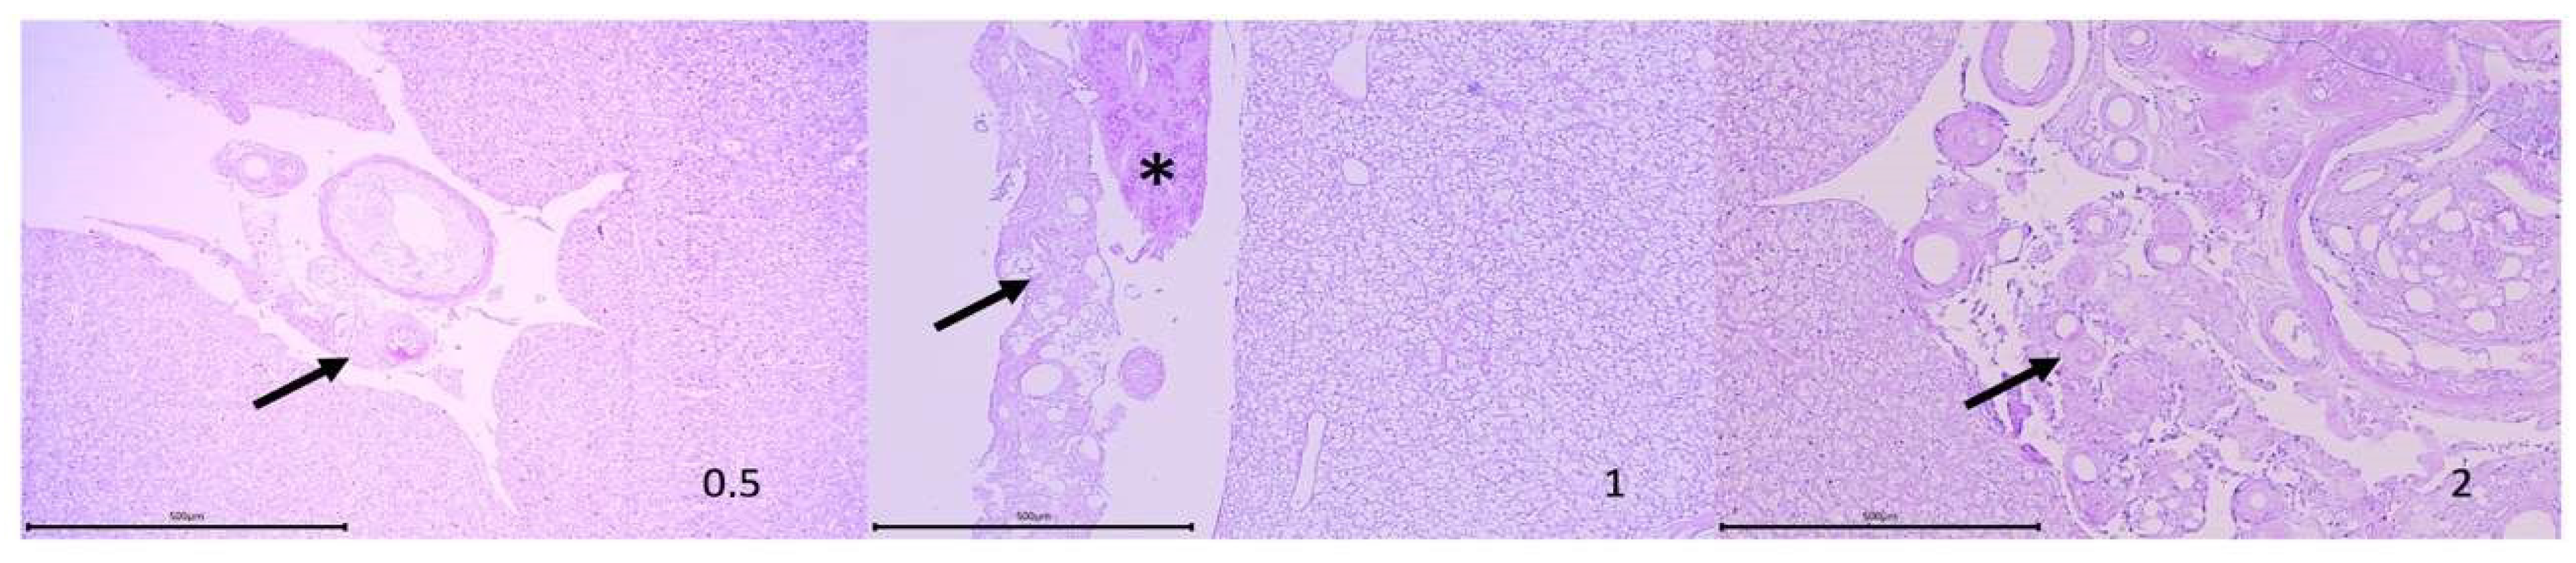

3.1. Macroscopic and Histological Effect of Vaccination

- Coscelli, G.A.; Bermúdez, R.; Losada, A.P.; Santos, Y.; Quiroga, M.I. Vaccination against Aeromonas salmonicida in turbot (Scophthalmus maximus L.): Study of the efficacy, morphological changes, and antigen distribution. Aquaculture 2015, 445, 22–32. [Google Scholar] [CrossRef]

- Noia, M.; Domínguez, B.; Leiro, J.; Blanco-Méndez, J.; Luzardo-Álvarez, A.; Lamas, J. Inflammatory responses and side effects generated by several adjuvant-containing vaccines in turbot. Fish Shellfish Immunol. 2014, 38, 244–254. [Google Scholar] [CrossRef]